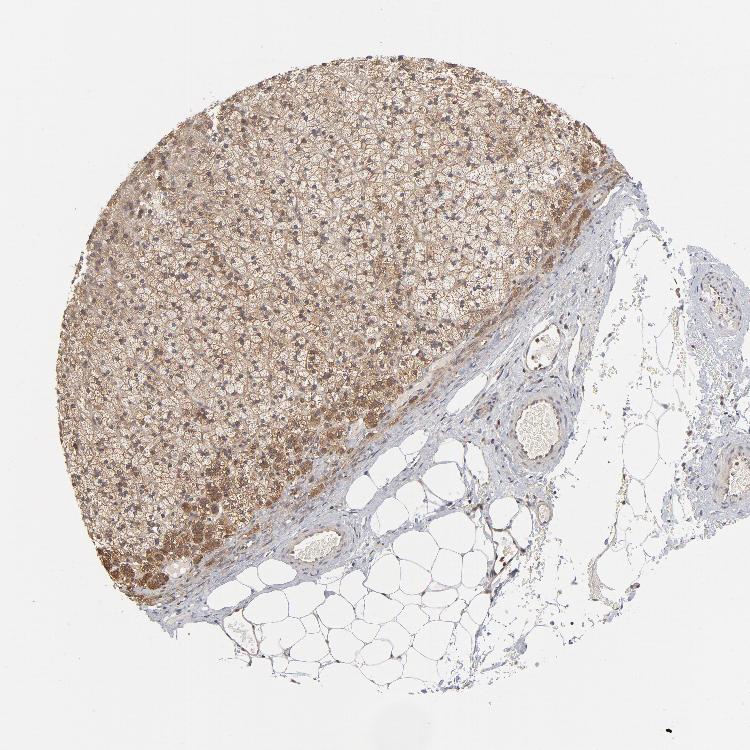

ADRENAL GLAND - Antibody stainingi

Antibody staining in the annotated cell types in the current human tissue is reported as not detected, low, medium, or high, based on conventional immunohistochemistry profiling in selected tissues. This score is based on the combination of the staining intensity and fraction of stained cells.

Each image is clickable and will lead to virtual microscopy that enables deeper exploration of all samples and also displays staining intensity scores, fraction scores and subcellular localization as well as patient and tissue information for each sample.

Antibody HPA003630Antibody HPA021865

Glandular cells LowHigh